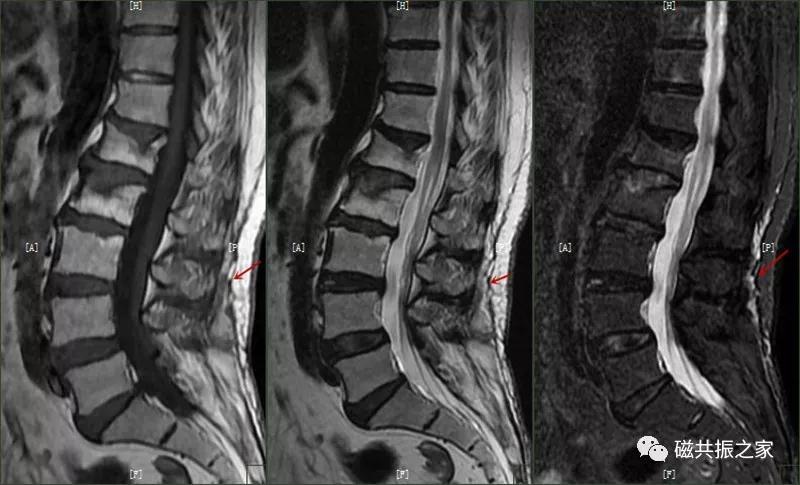

8.椎体骨折

椎体压缩性骨折常成前窄后宽的楔形改变,新鲜骨折(红箭头)常在T1WI呈低信号(出血时可呈高信号),T2WI呈低、中信号,在脂肪抑制的T2WI上呈高信号。椎体陈旧性骨折(白箭头)信号类似于正常椎体信号。如需了解脊柱骨折分型请查阅脊柱骨折的分型。